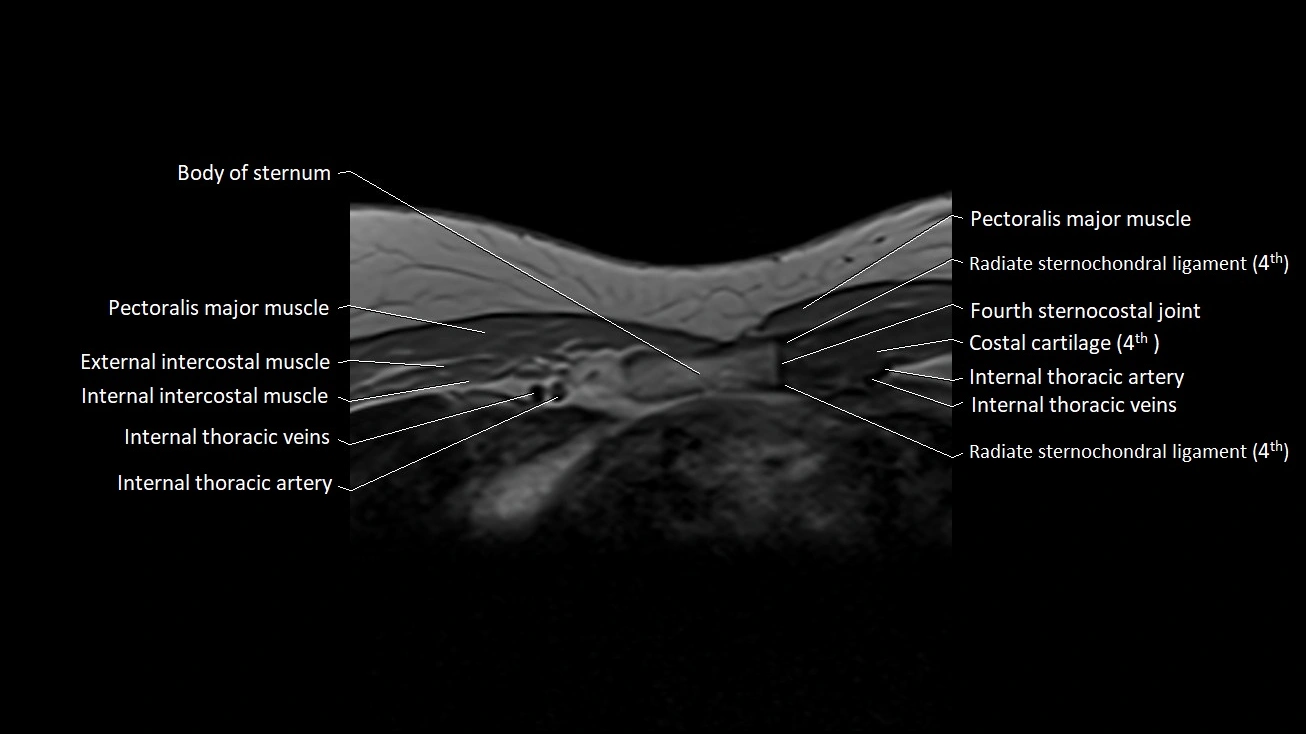

MRI images

image